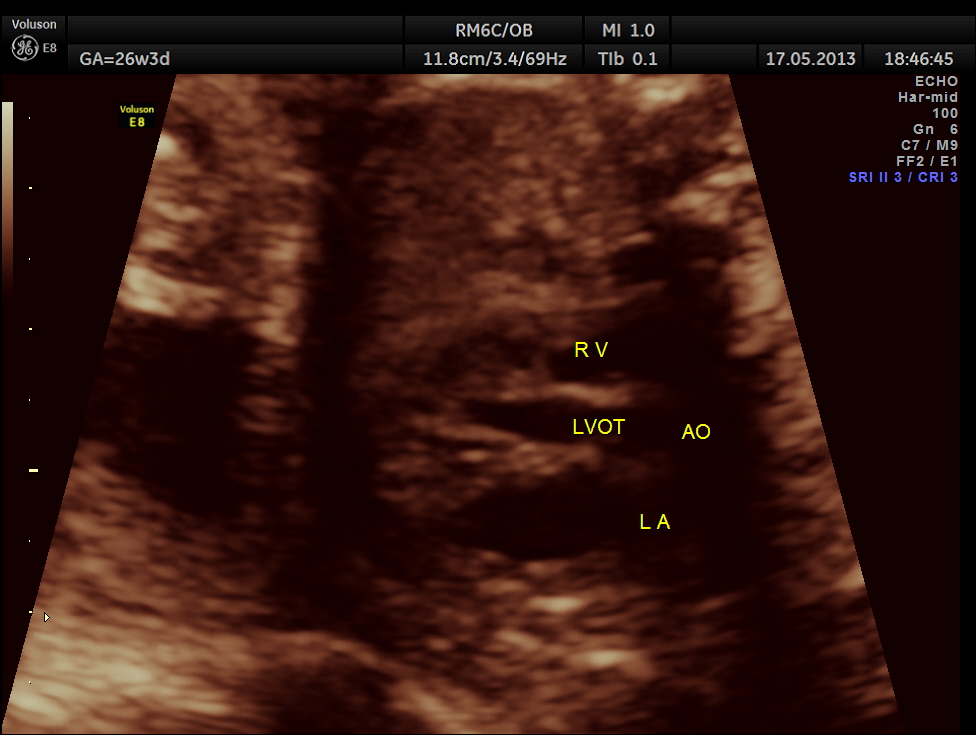

The following images show the sections of the heart.

This fetus did not show any oro-facial clefts ; heart and spine appeared normal.